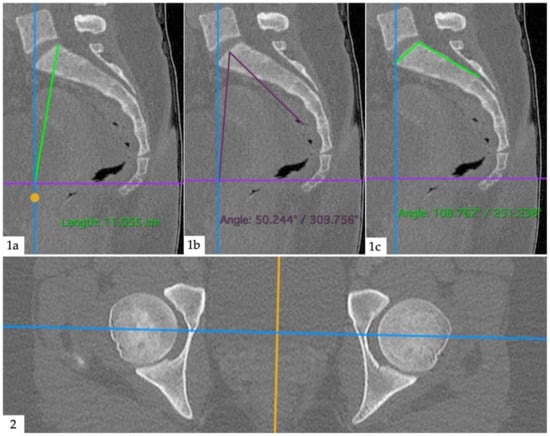

Anatomical measurements were performed by an orthopedic surgeon (M.M.) with the same software (Horos v3.3.6, The Horos Project, public license), using dynamic multiplanar reconstructions and triangulation. Pelvic radius (PR) was defined as the distance between the posterior–superior corner of the first sacral vertebra and the center of a line between the two femoral heads. Pelvic incidence (PI) was defined as an angle formed between a line from the center of a line between the two femoral heads and the center of the sacral plateau and a line perpendicular to the sacral plateau. Sacral table angle (STA) was defined as an angle between the posterior wall of the sacrum and the sacral plateau. An example image of the measurements is given as Figure 3. A junior radiologist (V.K.) performed measurements on 40 randomly selected sample patients to assess inter-reader agreement.

Figure 3. Anatomical measurements. (1a): Pelvic radius; distance between posterior–superior corner of the first sacral vertebra and the center of a line between the femoral heads (intersection between blue and violet lines). (1b): Pelvic incidence; angle between a line from the center of a line between the two femoral heads and the center of the sacral plateau and a line perpendicular to the sacral plateau. (1c): Sacral table angle; angle between the posterior wall of the sacrum and the sacral plateau. (2): Second plane (axial) to aid orientation.